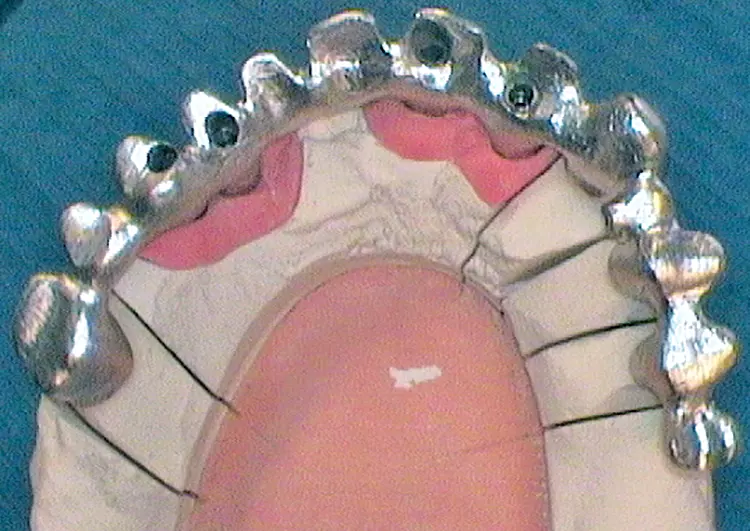

Nach Freilegung der Implantate regio 026,027 im Februar 2020, bei der auch die Implantation regio 037 (T3, Zimmer Biomet Dental, 4,0 mm x 13,0 mm) vorgenommen wurde (Abb. 32 OPG nach Freilegung), erfolgte im März nach Abformung mit offenem Löffel (open tray technique) und Gesichtsbogenregistrat die prothetische Versorgung mittels CAD/CAM gefräster Abutments (Dentaltechnik Hessel und Lutgen, Trier) und transversal verschraubter, verblockter VMK-Kronen (Abb. 33-36). Die Freilegung und Versorgung des Implantates 037 ist zusammen mit der Entfernung des Zahnes 38 für Juli 2020 geplant.